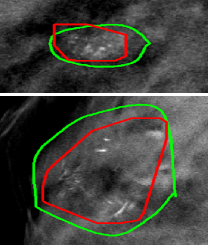

The proposed system was tested on an independent GE SenoClaire DBT volume set with 23 labeled malignant MC groups and 42 normal cases, no individual MC labeled and no other abnormalities visible. Figure 4(a) shows the MC group detection FROC and the comparison with other previously published MC group detection performances on DBT [1, 2, 3, 4, 5, 10]. Figure 4(b) shows two successful detections. The proposed system shows state-of-the-art performance compared with these published works, although all these works including ours were tested on different and relatively small datasets (23absent23\leq 23 cancerous lesions). We need to emphasize that there was absolutely no training or fine-tuning on the DBT data for our system, while other works were not restricted to develop on small numbers of DBTs that could cause overfitting. The study from Morra et al. [10] reported better performance, but the authors used Hologic cases with two-view DBT volumes per breast, which may double the chance to find MC groups, while the GE set we were using had only one DBT view available. Furthermore, there is no method details disclosed in [10].

(b) Detection examples

Figure 4: (a) Malignant MC group FROC tested on independent DBT volume set with comparison to other reported performances. (b) Examples of the output detections (red) and their corresponding truth contours (green) displayed in DBT slices.